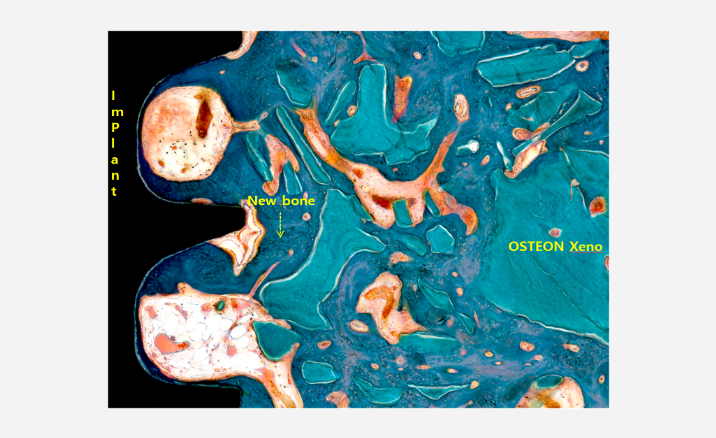

Resin 제작

Implant